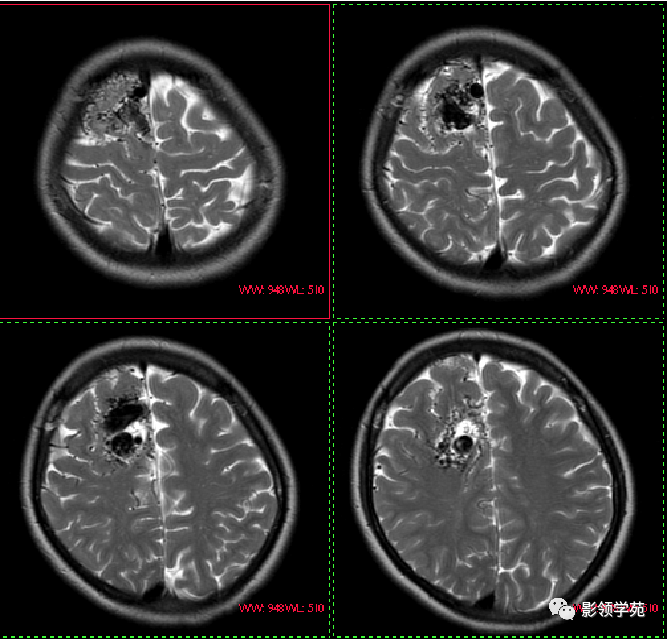

MRI表现:

一团匐行的具有流空效应的管道结构。MRA能显示AVM的全貌,供血动脉、迂曲血管团、引流静脉均为清晰的高信号影。

AVM-动静脉畸形